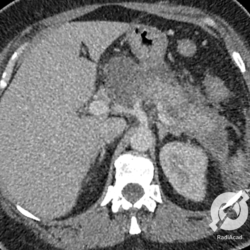

Embora o diagnóstico de pancreatite seja clínico e laboratorial, a tomografia é um excelente exame para avaliação da pancreatite aguda. O principal achado, assim como em qualquer abdome agudo, é a densificação do tecido adiposo adjacente ao pâncreas, em geral associada a um aumento de volume da glândula. Aqui observamos um pâncreas aumentado de volume e um borramento peripancreático inflamatório. Também podemos perceber a causa da pancreatite. Perceberam os cálculos biliares no hipocôndrio direito?

Pancreatite aguda aqui demonstrada na tomografia computadorizada, na qual observamos, no corte axial, um pâncreas aumentado e um borramento adiposo anterior. Já na reconstrução coronal, vemos a cabeça pancreática grande, com o borramento da gordura adjacente.